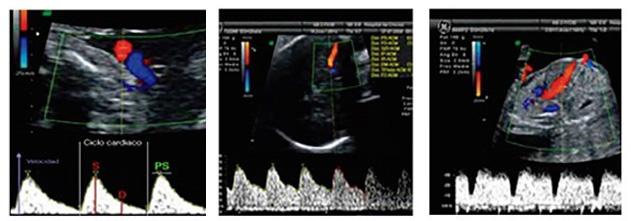

La ecografía doppler se reserva para estados fetales que muestren compromiso hemodinámico (fetos anémicos, RCIUs, gemelares monocoriales, preeclampsias, pretérminos severos), con la finalidad de detectar precozmente la insuficiencia placentaria y la hipoxia fetal. Se evalúan los siguientes vasos:

Arteria uterina

Arteria umbilical Arteria cerebral media Ductus venoso

Los hallazgos patológicos son ↓ flujo en arteria umbilical, ↑ flujo arteria cerebral media, Notch proto diastólico en arteria uterina y flujo reverso en ductus venoso.